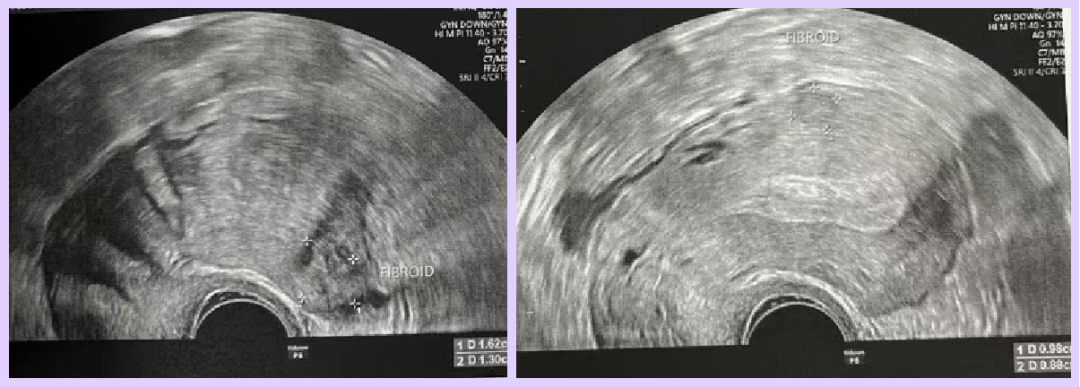

- The female patient also has uterine fibroids.

Both partners are of advanced reproductive age and had previously attempted IVF twice without success. After evaluation, the doctor diagnosed the female patient with diminished ovarian reserve (DOR) due to her age. Ultrasound revealed only 3 usable follicles (diameter > 4mm), indicating a significantly reduced ovarian reserve.

- Ultrasound Findings:

- Endometrial thickness: 5 mm

- Multiple uterine fibroids, largest measuring 24×13 mm